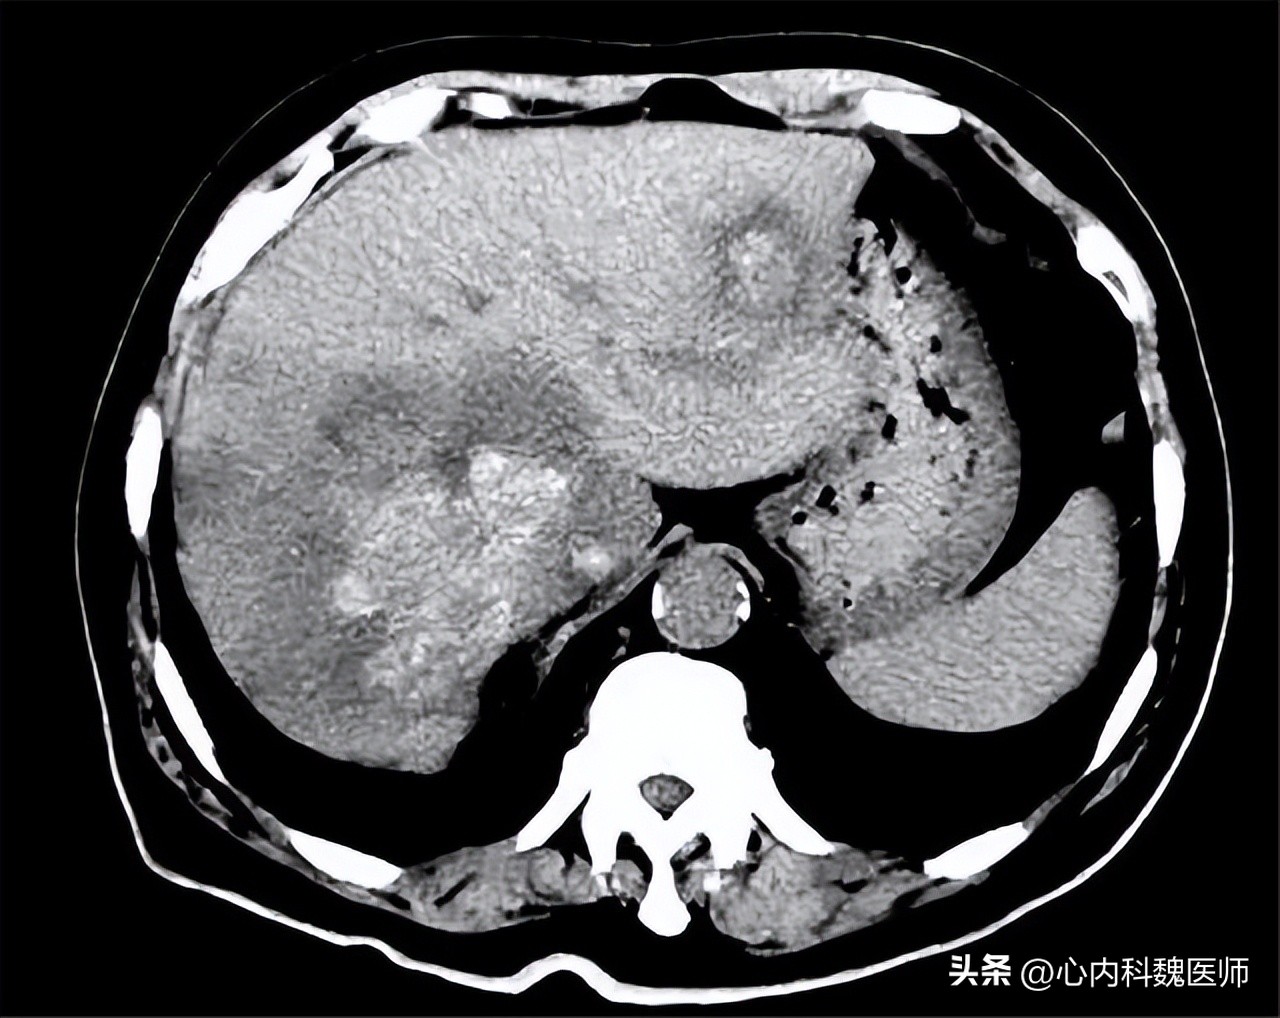

了解李先生基本情况,为李先生进行体格检查, 通过按压腹部位置可明显感觉脾大症状,观察巩膜发现轻微黄染,疑似黄疸症状; 随后通过听诊发现肝脏腹水现象,结果李先生乙肝病史, 初步推测李先生发生了肝硬化,立即进行肝功能检查,检查结果发生丙氨酸氨基转移酶升高,提醒肝病发生,总胆红素242μmol/L,提示为中度黄疸,Ⅲ型前胶原氨基端肽为203μg/L,提示肝脏纤维化。

肝脏影像检查发生肝脏有肿胀现象, 肝硬化患者会出现免疫功能下降,为李先生监测免疫功能,检查结果发现免疫细胞 CD3,CD4均有减少现象, 病毒检测发现乙型肝炎病毒呈阳性,确定是 由慢性乙肝转化为肝硬化。